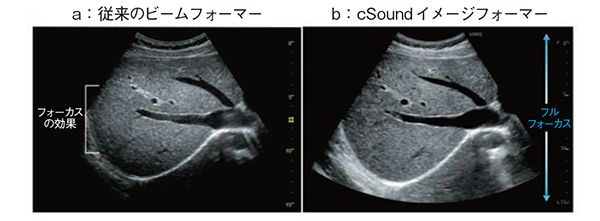

このようなcSoundイメージフォーマーの新しい画像構築技術により,実際の画質がどのように変化するのかを図4に示す。深部から浅部まで高い均一性と空間分解能を実現している。また,1回の送受信で広範囲の画像情報を取得することで,送信回数を増やすことなく高いフレームレートを実現している。そして,S/Nを上げているため,ノイズがきわめて少なく,高いコントラストを実現できる。このような画像構成方法は,Bモードのみならず,カラードプラ,パルスドプラ,造影など,すべての基本モードにおいて応用され,高いフレームレート,高感度,微細な表現が可能となっている。

図4 cSoundイメージフォーマーがもたらす高画質

従来の方式で取得した画像(a)に比べ,近位部の画質向上,深部までの高い均一性と透過性,高フレームレート(リアルタイム性)を同時に実現することが可能である(b)。